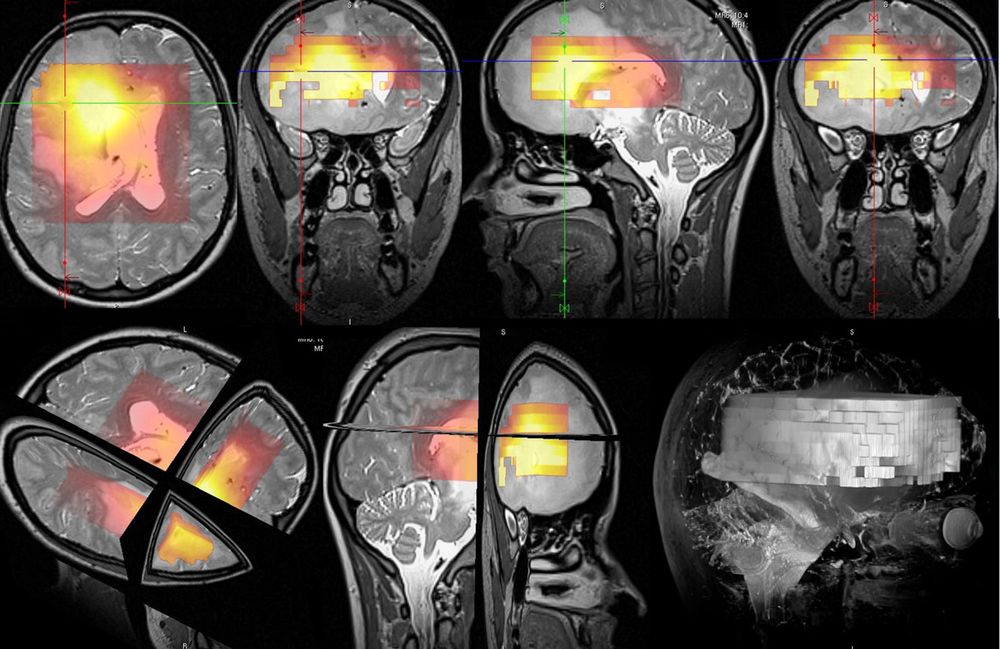

Přednáška pro Lékařskou fakultu v Hradci Králové (molekulární a buněčné zobrazování, MR spektroskopie)